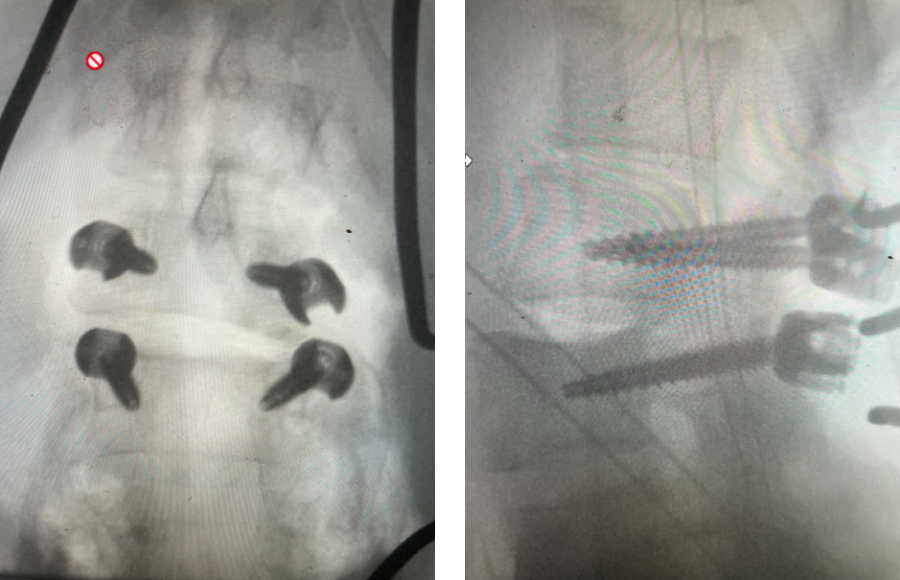

Fig 1: Plain X-rays demonstrating a grade 1 L45 spondylolisthesis with dynamic translation of approximately 4 mm (arrow).

Plain lumbar x-rays were done with flexion/extension views. Surprisingly the patient had 4 mm of anterior translation and slight angulation in flexion (Fig 1). This was unexpected because in degenerative spondylolisthesis the patient more commonly has auto stabilized by formation of stabilizing arthritic structures and has no motion on dynamic x-rays. However, approximately 20% of patients will have some degree of translation on flexion-extension x-rays with degenerative L4-5 spondylolisthesis. Because she had failed all means of conservative management, it was felt that the patient would benefit by a lumbar decompression and instrumented fusion because of the acute instability demonstrated on x-rays and her age.

Fig 5: intraoperative fluoroscopic images demonstrating L2-3 screw placement.